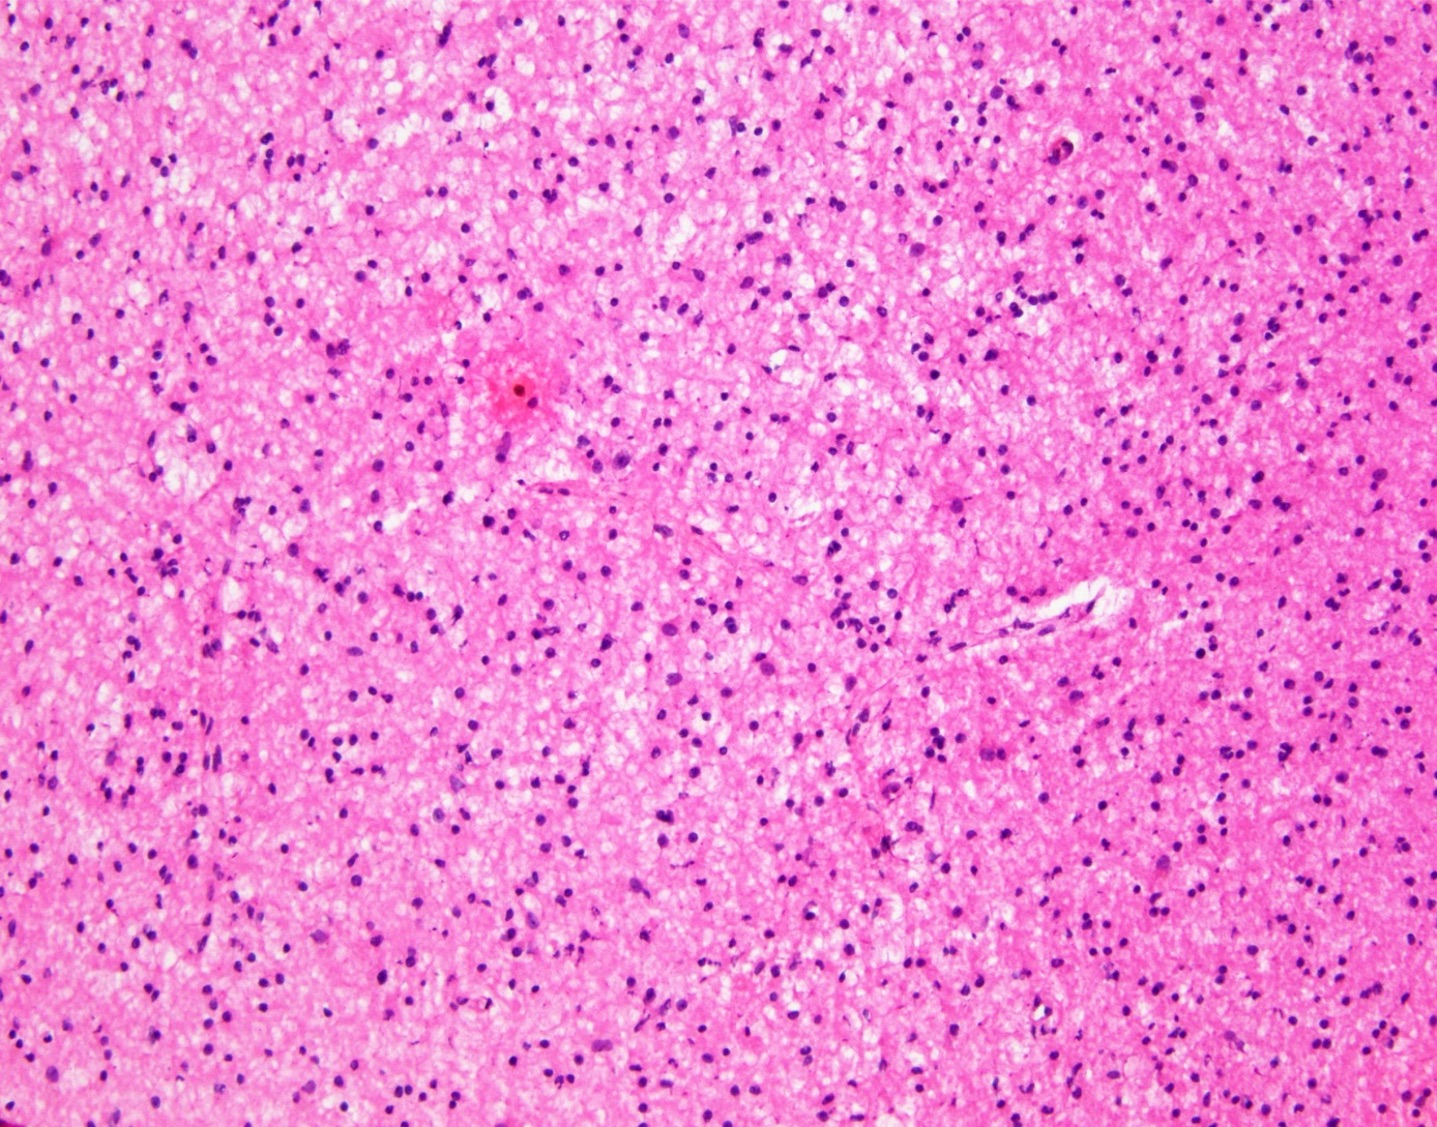

Microscopic (histologic) description

- Closely packed cells with small, round, monotonous nuclei (slightly larger than a normal oligodendrocyte)

- Perinuclear clearing (fried egg appearance)

- Formalin fixation artifact

- Will not be seen on frozen sections or smear preparations

- Network of thin walled, branching blood vessels (chicken wire vasculature)

- Microcalcifications (calcospherites) are characteristic

- Presence of perineural, perivascular or subpial aggregates of tumor cells (secondary structures of Scherer)

- Occasional mitoses and moderate nuclear atypia are still consistent with grade 2 designation (J Neuropathol Exp Neurol 2001;60:248)

- Not uncommon to find well differentiated / fibrillary astrocytic morphology (Acta Neuropathol 1984;64:265)

- Features of CNS WHO grade 3 oligodendroglioma:

- Presence of microvascular proliferation

- Presence of necrosis

- Presence of brisk mitotic activity

- Strict mitotic figure cutoffs do not currently exist; some authors suggest ≥ 6 mitoses per 10 high power fields for WHO grade 3 designation in tumors without necrosis or vascular proliferation (Neuro Oncol 2014;16:1244, Neuro Oncol 2016;18:888)

Microscopic (histologic) images

Contributed by Jared T. Ahrendsen, M.D., Ph.D. and John DeWitt, M.D., Ph.D.